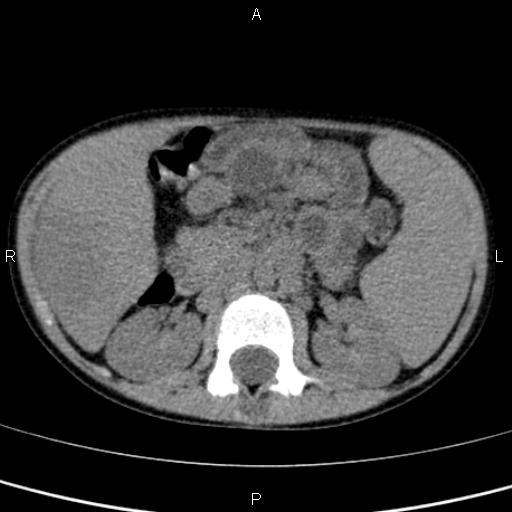

Абсцесс печени — заболевание, возникающее в результате гнойного воспаления тканей печени, их отмирания и образования полости, заполненной гноем . . . . фото, признаки и лечение . . .

Абсцесс (от лат . abscessus — «гнойник», «нарыв») печени представляет собой единичное или множественное очаговое воспаление с образованием в ткани печени одного или нескольких опухолевидных . . .

Абсцесс печени также может возникнуть после ранений, травм или операций . Клинические проявления: лихорадка, боли в правом подрёберье и правой боковой области, слабость, потливость .